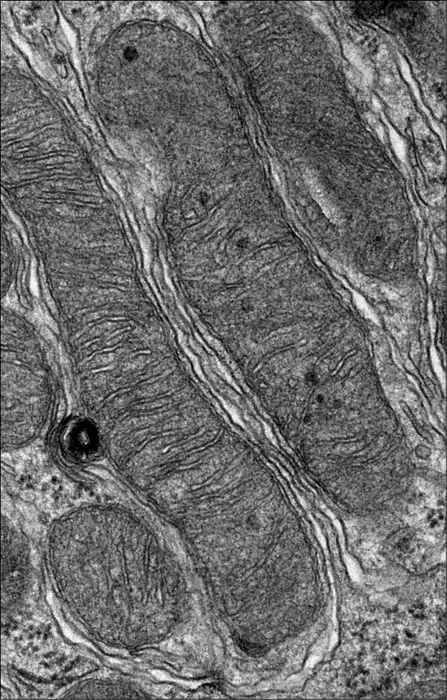

Electron microscope image of mitochondria treated with a drug that prevents AKI. Even under severe kidney stress, the mitochondria are appropriately long and skinny and are functional.

Rebekah Nicholson and Linda Nikolova